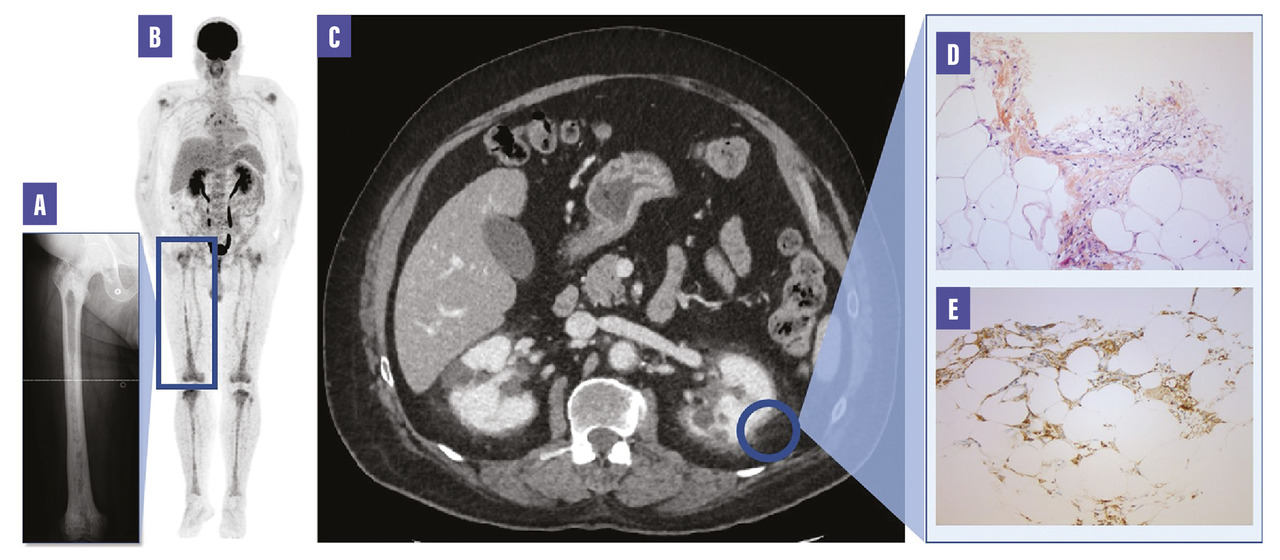

Un homme de 71 ans présente un syndrome polyuropolydipsique révélant un diabète insipide. L’anamnèse note également des douleurs d’horaire mixte des jambes. L’examen clinique est sans particularité en dehors d’une gynécomastie bilatérale expliquée par un hypogonadisme hypogonadotrope. Les examens morphologiques et fonctionnels objectivent une atteinte des os longs (fig. A et B ) et un aspect de reins « chevelus » (fig. C ). La fonction rénale est normale. La biopsie de graisse périrénale (fig. D et E ) permet de porter le diagnostic de maladie d’Erdheim-Chester.

La maladie d’Erdheim-Chester est une histiocytose non langerhansienne rare, plus fréquemment rapportée chez les hommes, avec un âge moyen d’environ 50 ans. C’est une maladie de présentation clinique très variée, allant de l’atteinte unifocale à l’atteinte multisystémique, tous les organes et systèmes pouvant être infiltrés. L’atteinte sclérotique douloureuse multifocale des os longs et le diabète insipide d’origine centrale sont fréquemment rencontrés. Le pronostic est fonction des atteintes extra-osseuses.

Le diagnostic peut être difficile et retardé. L’analyse histologique d’un tissu atteint permet de confirmer le diagnostic (infiltration par des histiocytes spumeux CD68+, CD1a-, S100-) et de rechercher les mutations permettant une thérapie ciblée, en particulier la mutation BRAFV600E. Le traitement, notamment par thérapie ciblée (inhibiteur de BRAF ou de MEK) lorsqu’une mutation est mise en évidence, est indiqué chez les patients symptomatiques et/ou présentant une dysfonction d’organe ou une atteinte du système nerveux central.1, 2